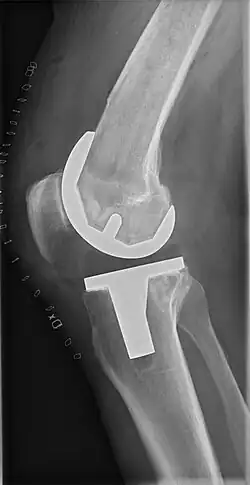

Knee replacement, also known as knee arthroplasty, is a surgical procedure to replace the weight-bearing surfaces of the knee joint to relieve pain and disability, most commonly offered when joint pain is not diminished by conservative sources.[1][2] It may also be performed for other knee diseases, such as rheumatoid arthritis. In patients with severe deformity from advanced rheumatoid arthritis, trauma, or long-standing osteoarthritis, the surgery may be more complicated and carry higher risk. Osteoporosis does not typically cause knee pain, deformity, or inflammation, and is not a reason to perform knee replacement.

Knee replacement surgery can be performed as a partial or a total knee replacement.[3] In general, the surgery consists of replacing the diseased or damaged joint surfaces of the knee with metal and plastic components shaped to allow continued motion of the knee.